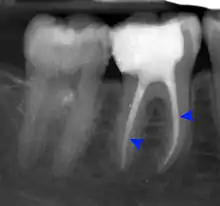

- Radiographs utilized to find dental caries and bone loss laterally or at the apex.

Decay (green) with apical abscess (blue)

Gutta-percha point indicating abscess origin